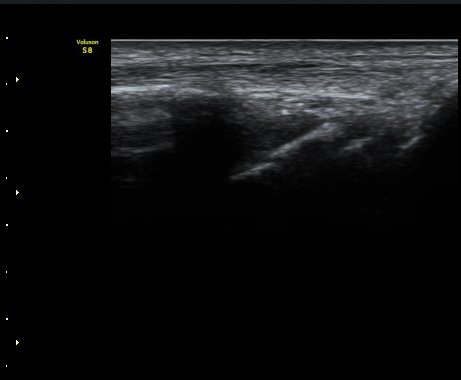

ÃÊÀ½ÆÄ °Ë»ç

ÁÖ»ó°ñ ¼±»ó°ñÀýÀº ´Ü¼ø¹æ»ç¼± ÃÔ¿µ ½Ã È®ÀεÇÁö ¾ÊÀº °æ¿ì°¡ ¸¹Àºµ¥ ÀÌ ¶§ ÃÊÀ½ÆÄ

°Ë»ç°¡ ÁÖ»ó°ñ °ñÀý Áø´Ü¿¡ ¸Å¿ì À¯¿ëÇÏ´Ù. ±×·¯¹Ç·Î ¼Õ¸ñ ´ÙÄ£ ÈÄ Áö¼ÓÀûÀÎ ÅëÁõÀ»

È£¼ÒÇϰí ÁÖ»ó°ñ ºÎÀ§ ¾ÐÅëÀ» º¸ÀÌ´Â °æ¿ì ÃÊÀ½ÆÄ°Ë»ç¸¦ ½ÃÇàÇÏ¿© ÁÖ»ó°ñ °ñÀý ¿©ºÎ¸¦

È®ÀÎÇØ¾ß ÇÑ´Ù.

ÃÊÀ½ÆÄ°Ë»ç¸¦ ½ÃÇàÇÒ ¼ö ¾ø´Â °æ¿ì´Â ÄÄÇ»ÅÍ ÃÔ¿µ°Ë»ç¸¦ ÁÖ»ó°ñ °ñÀýÀ» È®ÁøÇÒ ¼ö ÀÖ´Ù.